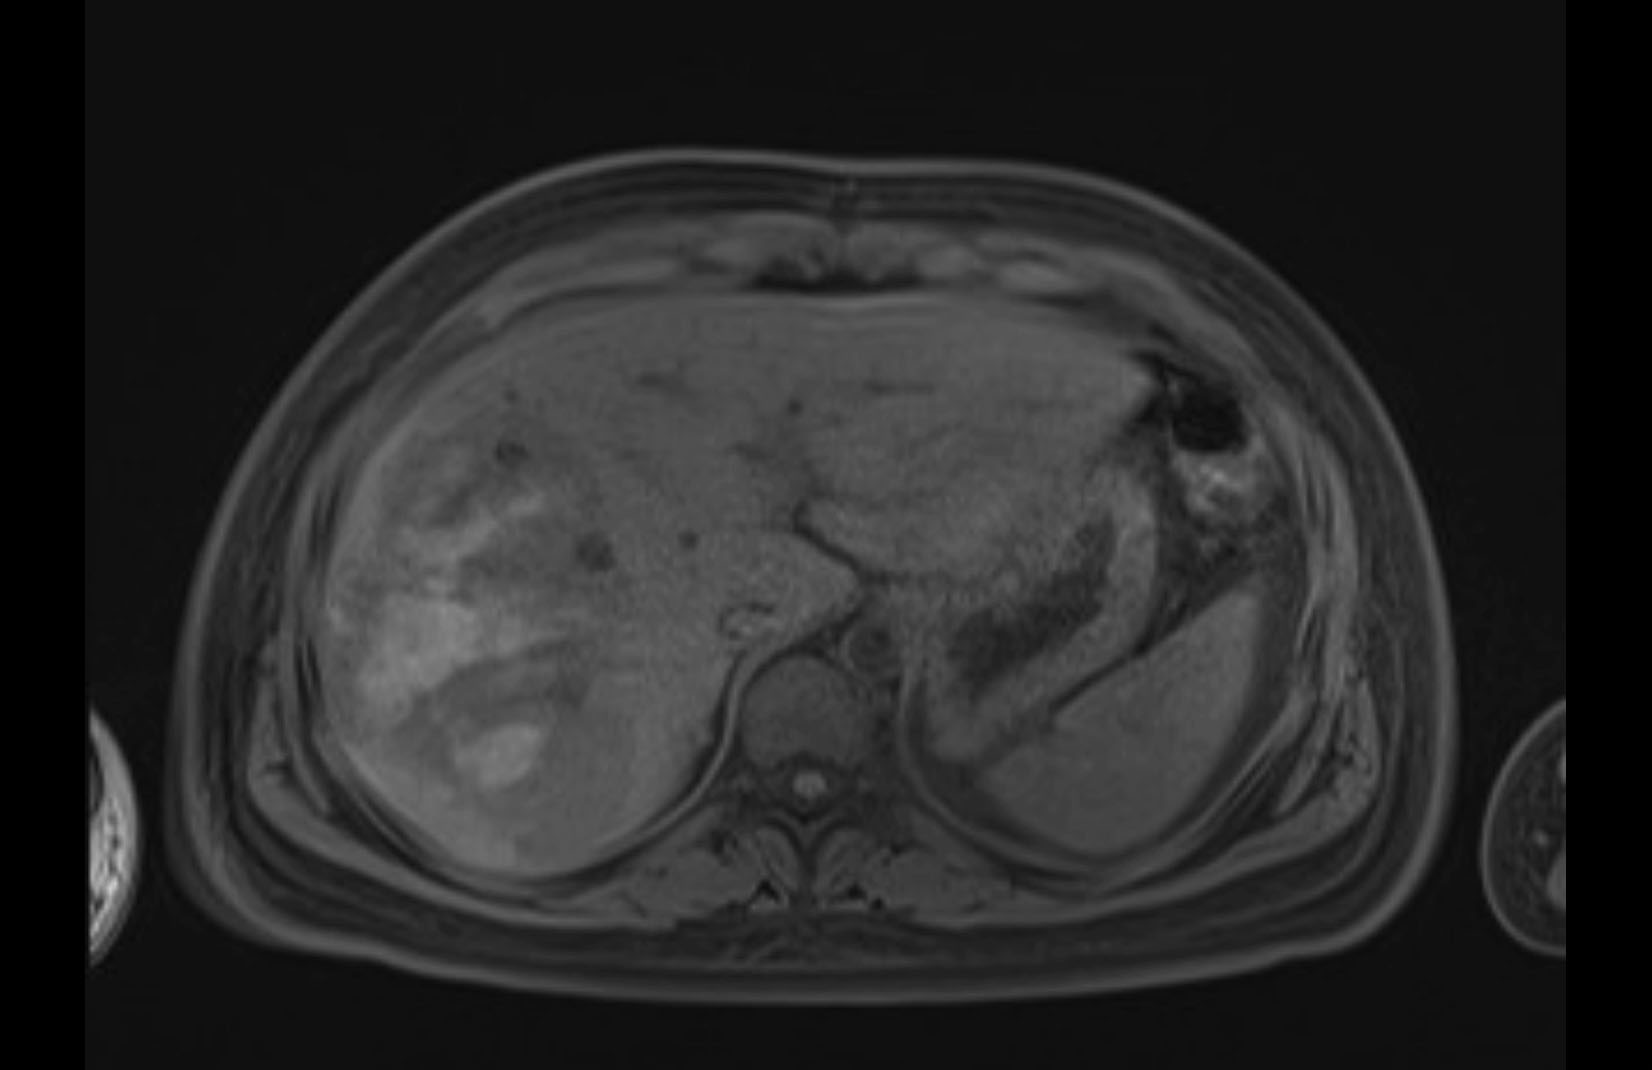

Imaging Analysis

Look through the patient's CT scan to identify any areas of concern for the necessary procedure.

MRI T1

Based on initial findings, which issue(s) would you be most concerned about?